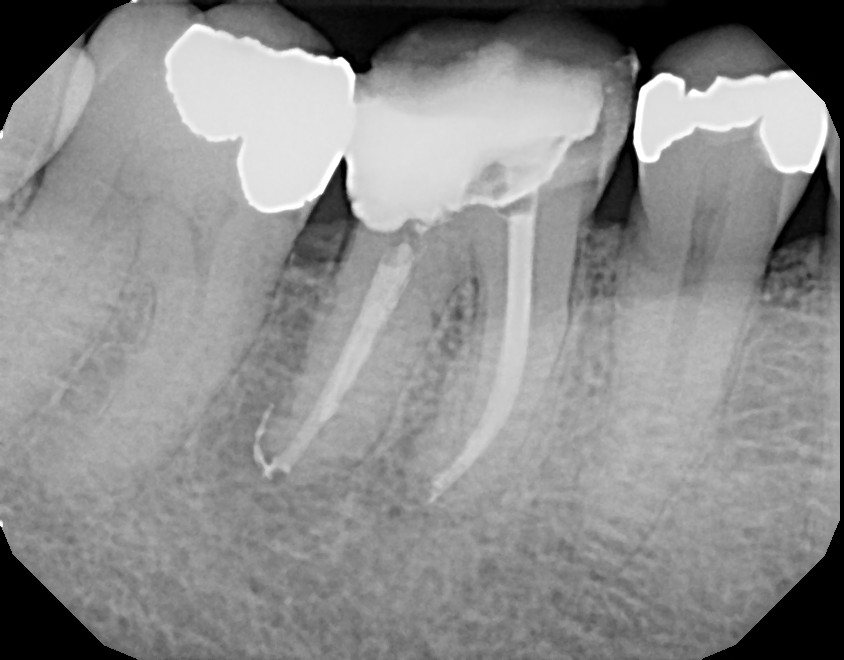

This is a first mandibular molar (tooth #30). The patient experienced no pain and had no check up for over one year. A deep cavity was present which caused an infection, requiring a root canal. If this patient waited longer, they could have lost the tooth because of how quickly the cavity was growing. Always get your 6 month check ups to avoid costly procedures. This tooth will also require a crown along with a few adjunctive procedures.